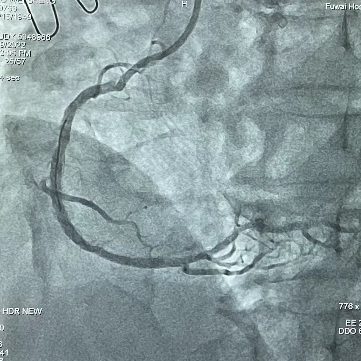

患者为73岁男性,自述间断胸闷已9年有余,近半年胸闷症状复发;经冠脉造影显示,患者右冠状动脉远段有明显狭窄,狭窄率90%,靶血管严重钙化,病变长度目测40mm,参考血管直径为3mm,未见夹层产生,TIMI血流3级,在心脏搏动和不搏动时皆可见清晰高密度影。

在局部麻醉下,经右侧远端桡动脉入路,首先对靶血管进行球囊预扩,然后术者先将2.75*12mm冲击波冠脉球囊送至靶血管近端,并在4atm低压扩张后启动脉冲放电,持续一个治疗周期;然后更换3.0*12mm冲击波冠脉球囊,再次送至靶血管远端,再次进行一个治疗周期的脉冲放电。整个治疗过程总计进行了2个放电治疗周期(总计20次脉冲),钙化斑块被安全地“压裂“,靶血管管腔获得良好,植入串联双支架后经冠脉造影检查显示,支架贴壁良好,未见夹层与血栓,目测残余狭窄0%。